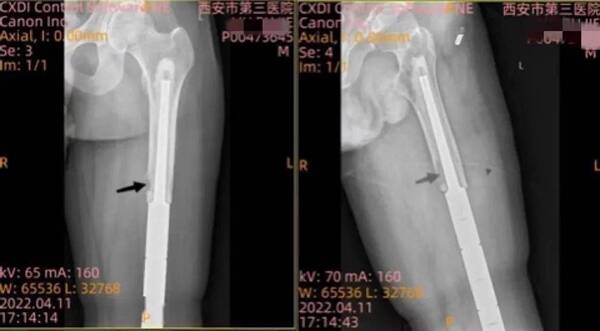

誰(shuí)曾想厄運(yùn)再次降臨,在兩年后的一次復(fù)查中,行X線檢查時(shí)再次發(fā)現(xiàn)小劉患肢的股骨中段皮質(zhì)破壞,在置換的股骨假體結(jié)合部位出現(xiàn)腫瘤復(fù)發(fā)。MRI提示:左股骨中段異常軟組織影,考慮復(fù)發(fā);胸部CT提示:散在小結(jié)節(jié)。于西安市第三醫(yī)院行左大腿切開活組織檢查后病理提示:(左股骨)纖維組織內(nèi)查見(jiàn)嗜酸性腫瘤細(xì)胞浸潤(rùn)性生長(zhǎng),考慮 腺泡狀軟組織肉瘤復(fù)發(fā)。

(箭頭處為腫瘤復(fù)發(fā)部位)